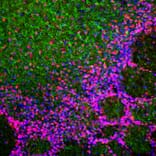

Immunofluorescent analysis of rat cerebellum section co-stained with Anti-a-Synuclein Antibody, at a dilution of 1:1,000, in red, and Anti-GFAP Antibody (A85419 | 1:5,000, in green. The blue is DAPI staining of nuclear DNA. Following transcardial perfusion of rat with 4% paraformaldehyde, brain was post fixed for 24 hours, cut to 45µM, and free-floating sections were stained with the above antibodies. The a-synuclein protein is concentrated in synaptic regions, while the Anti-GFAP Antibody stains the filamentous cytoskeleton of Bergmann glia and astrocytic cells.